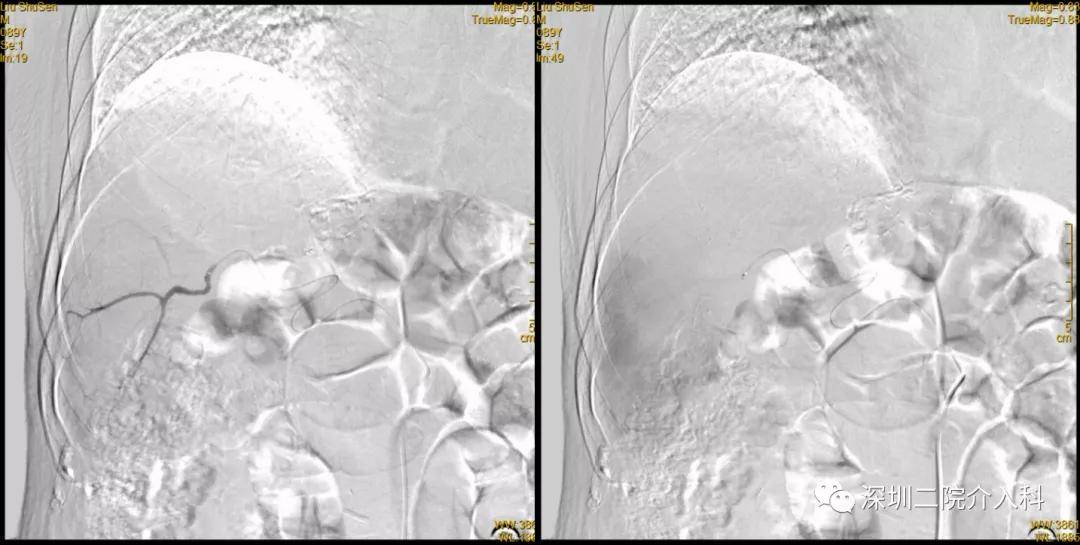

超选至肝右动脉分支1造影+栓塞

栓塞材料:表柔比星60mg+载药

微球;明胶海绵

超选至肝右动脉分支2造影+栓塞

微球、碘油;明胶海绵